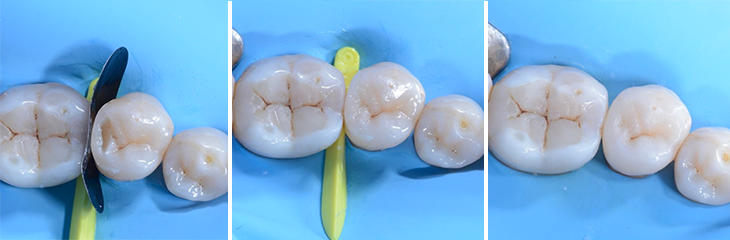

9. Restauration de la paroi distale interproximale

11. Cavité occlusale remplie de composite avant la finition et le polissage

12. Vue post-opératoire de la restauration